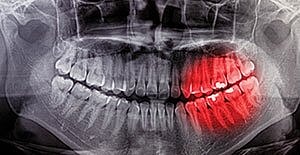

Teeth that are badly damaged or decayed can harm oral health and are generally pulled if they cannot be saved. An extracted tooth not only keeps the mouth from harm, but paves the way for dental implants, which restore health and beauty to the mouth.